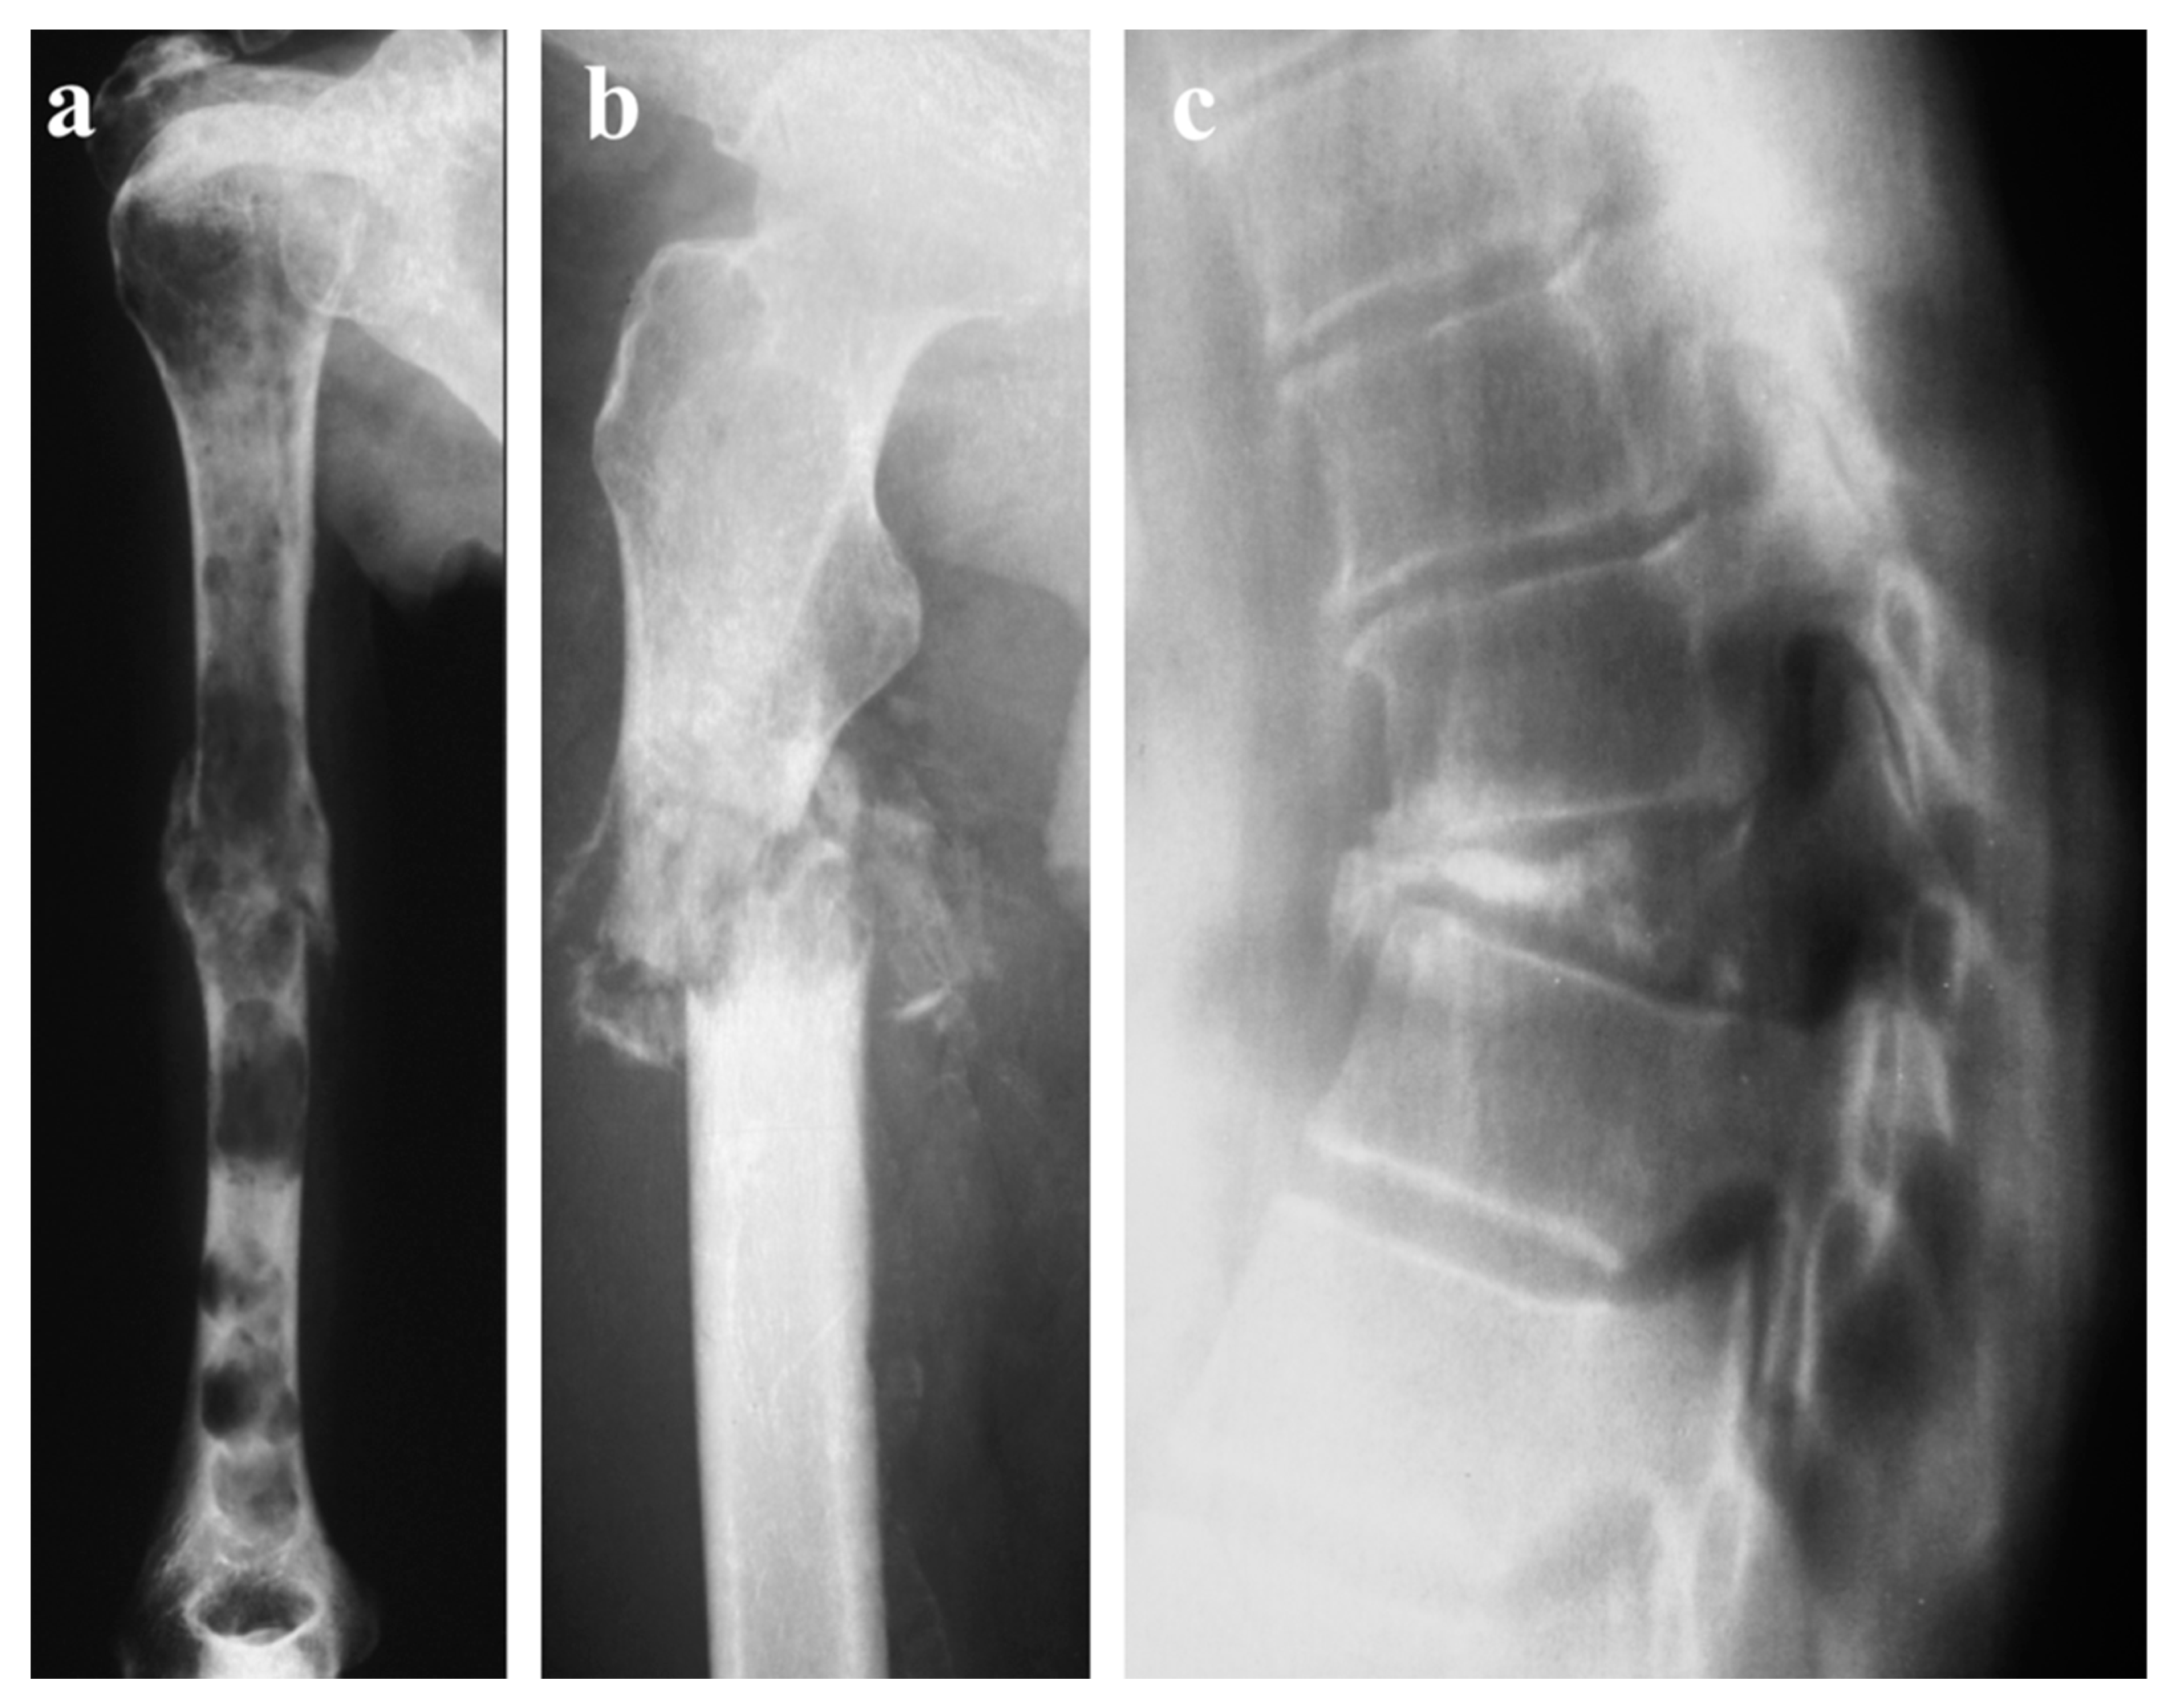

- Patnaik, S.; Yarlagadda, J.; Susarla, R. Imaging features of Ewing’s sarcoma: Special reference to uncommon features and rare sites of presentation. J. Cancer Res. Ther. 2018, 14, 1014–1022. [Google Scholar] [CrossRef]